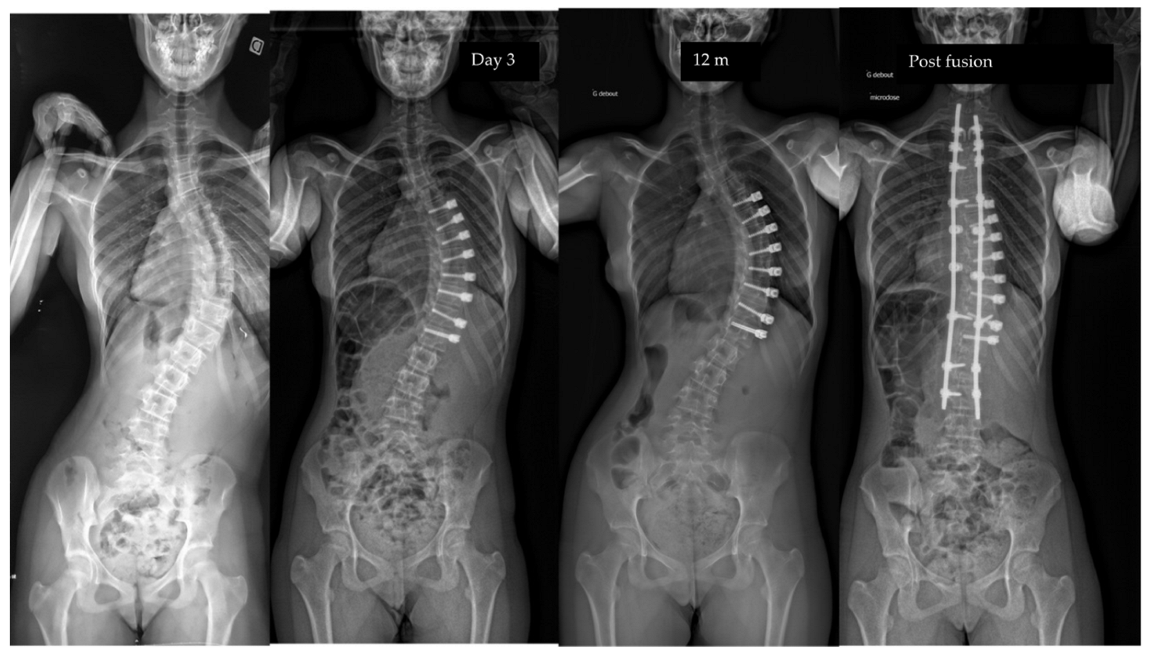

| Pre-op | Post-op Day 3 | Post-op 1y | Last f/u | p-Value | |

|---|---|---|---|---|---|

| Major curve | 49°(8,9°) | 27°(12°) | 22°(12°) | 19°(14°) | <0.01 |

| Secondary curve | 27°(14°) | 23°(15°) | 22°(11°) | 17°(10°) | <0.01 |

| Instrumented curve | NA | 26°(11°) | 23°(10°) | 20°(14°) | <0.01 |

| Kyphosis (T1–T12) | 20°(13°) | 23°(13°) | 25°(12°) | 24°(14°) | 0.06 |

| Lordosis (L1–L5) | 36°(12°) | 32°(13°) | 40°(7°) | 40°(8°) | 0.07 |

| Overcorrection | 10 (11%) | 10 right thor. | 5 tether release | Between 1,5, and 2 y po |

| Curve progression | 5 (2 adding-on) (5%) | Thor. | Fusion | 1 y po |